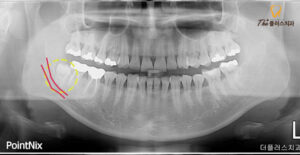

파노라마 사진을 보시면

신경관과 사랑니가 맞물려 있는 모습을

보실 수 있는데 이런 경우

안정적인 진행을 위해 CT를 촬영하여

사랑니의 정확한 맹출 방향과 치근의 휨 정도,

신경과 중첩된 모양 모두 정밀히 파악하여

발치를 진행해야 합니다.

또한 환자분의 경우

앞쪽에 위치하고 있는 치아와 근접해 있었기 때문에

발치 하면서 앞 치아의 크라운을 건드리거나

치아가 손상되지 않도록 해야 하는

고난이도의 수암동치과 사랑니발치 케이스였습니다.